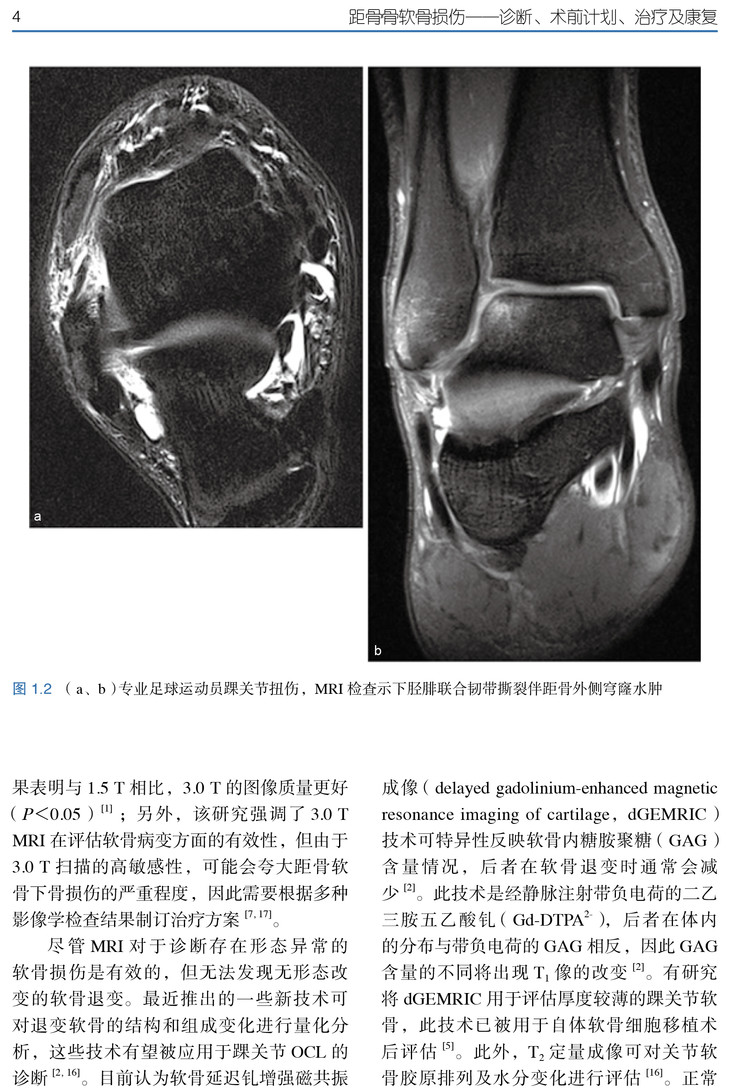

★ 内页插图 ★